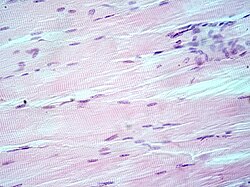

Hematoksilin-eozin bojilo ili HE bojilo je najčešće primjenjivana metoda bojenja u histologiji. Hematoksilin je bazično bojilo koja daje plavoljubičasto obojenje kiselim komponentama stanice, dok je eozin kiselo bojilo koja daje crveno-ružičasto obojenje bazičnim komponentama. Razlog zbog čega je baš ova metoda vodeća metoda bojenja već dugi niz godina je taj što se kombinacijom ovih bojila može obojiti cijela stanica i svi njezini dijelovi. Također, hematoksilin i eozin će dati takva obojenja koja se mogu lako razlikovati jedna od drugih što može uvelike pomoći u analizi i dijagnostici (McCann, 2015.). [1]

Eozin (prema grč. ἕως: zora, jutarnja rumen) je sjajnocrveno ksantensko bojilo, prvi put pripravljeno 1874. Eozin je kalijeva ili natrijeva sol tetrabromfluoresceina koji se dobiva adiranjem (dodavanjem) broma na fluorescein suspendiran u alkoholu. Mnogo se upotrebljavao u tekstilnoj industriji za bojenje svile i vune, a danas se koristi u fotografiji i kozmetici, za bojenje mikroskopskih preparata (zajedno s hematoksilinom), pripravu crvene tinte i drugo. [4] Eozin je ustvari naziv nekoliko fluorescentnih kiselih kemijskih spojeva koji se vežu i tvore soli s osnovnim, odnosno eozinofilnim spojevima poput bjelančevina koji sadrže aminokiselinske ostatke poput arginina i lizina, a boji ih tamnocrvenom ili ružičastom bojom kao rezultat djelovanja broma na fluorescein. Uz bojenje bjelančevina u citoplazmi, može se koristiti za bojenje kolagena i mišićnih vlakana za ispitivanje pod mikroskopom. Strukture koje se lako boje eozinom nazivaju se eozinofilnima. U području histologije, eozin Y je oblik eozina koji se najčešće koristi kao histološko bojilo. [5] [6]